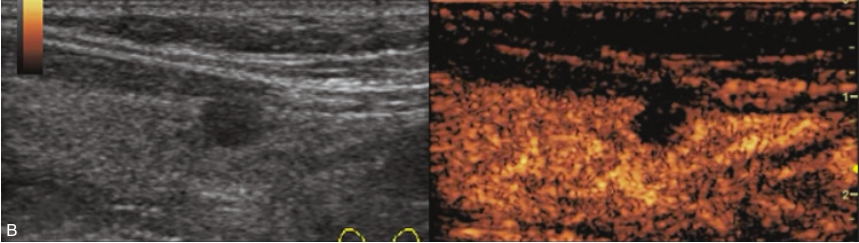

甲状腺左叶中下部见一混合回声结节,边界清,形态规则,中心部可见斑状强回声,CDFI显示周边可见环状血流信号,其内可见丰富血流信号,见图1-3-18。

该结节早于周围腺体组织增强,结节内部呈高增强表现,可见部分无增强区;结节晚于周围腺体组织消退,仍呈高增强表现;结节周边可见均匀高增强环,甲状腺被膜未见明显中断,见图1-3-19、ER1-3-9。

(1)结节增强早期早于腺体增强或与腺体同步增强,增强晚期晚于腺体消退或与腺体同步消退。

(2)结节内部呈均匀或不均匀弥漫性等增强或高增强,增强水平通常高于周围腺体。

(3)结节与周围腺体分界清晰,形态较规则。

(4)部分结节周边可见均匀高增强环。

(5)结节周边被膜连续完整。

甲状腺滤泡性腺瘤通常为富血供病灶,其增强水平等于或高于周围腺体,并呈现“早增强,晚消退”的特点,重点需要与滤泡性腺癌鉴别,腺瘤多边界清晰、形态较规则,造影时结节周围的高增强环厚薄一致、较为均匀,结节周边被膜连续完整、无浸润表现,颈部淋巴结无异常肿大等。而滤泡性腺癌边界不清、呈浸润性生长表现,周边高增强环消失或厚薄不均,如发现颈部异常肿大淋巴结及被膜连续性中断等,需要高度警惕甲状腺恶性肿瘤。

图1-3-18 甲状腺滤泡性腺瘤常规超声声像图

A.甲状腺左叶纵切面超声图像;B.结节内部点状及斑状强回声;C.CDFI血流图